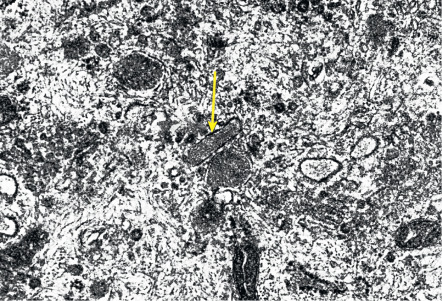

At the ultrastructural level, vascular endothelial cells are characterized by tight junctions between neighboring cells and by specialized organelles, the rod-shaped Weibel–Palade bodies ( Fig. 102.5 ), that serve as storage organelles for the coagulation factor von Willebrand factor, also known as factor VIII-related antigen. Weibel–Palade bodies also contain P-selectin, angiopoietin-2, and endothelin-1. Activation of endothelial cells by proinflammatory cytokines or pro-angiogenic factors readily leads to translocation of these storage organelles to the cell membrane, with consecutive enhanced membrane expression of P-selectin and release of von Willebrand factor. Other characteristic ultrastructural features include caveolae (minute invaginations of the membrane surface), pinocytotic vesicles, and the formation of vesiculo-vacuolar organelles (VVOs) . Circulating macromolecules cross the endothelium through interendothelial cell gaps and transendothelial cell pores, some of which arise from VVOs. Endothelial cell fenestrations, areas with direct apposition of the endothelial cell membranes without intervening cytoplasm, are rarely seen in normal skin except in angiogenic perifollicular blood vessels during the growth phase of the hair follicle. However, fenestrated endothelial cells are frequently seen in skin diseases with pronounced angiogenesis and vascular hyperpermeability, including psoriasis.